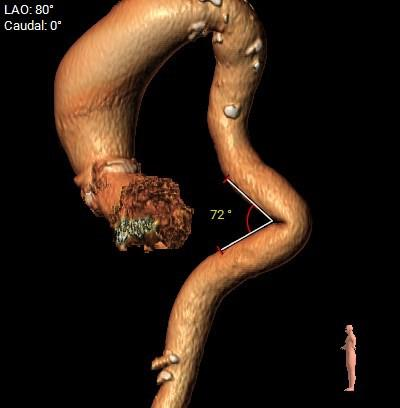

瓣环角度及弓角弓距

◇ 主动脉瓣环水平夹角52°,非横位心,主动脉弓角度较锐(43°)及弓距偏短;

◇ 外周入路血管走形迂曲,降主动脉有较锐夹角,主动脉弓,降主动脉,胸主动脉,腹主动脉有附壁钙化分布,血管内径可。